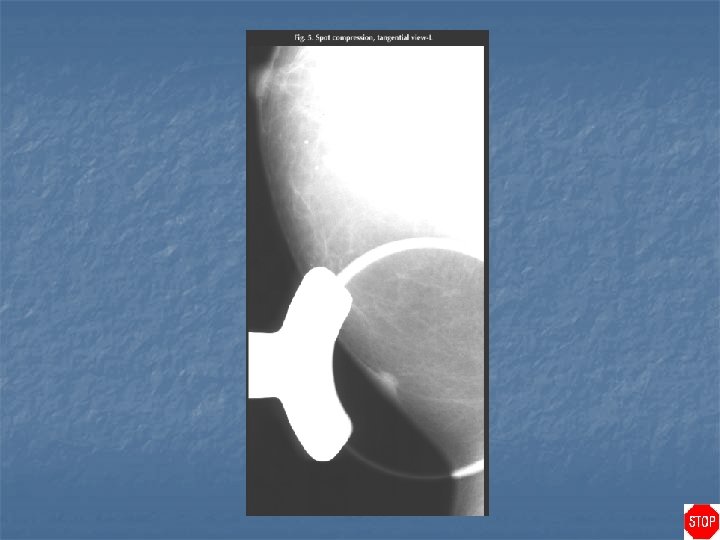

Case directory Sebaceous cyst (epidermal inclusion cyst) n n n Round, smoothly bordered mass that often abuts the skin surface Mass projects into the subcutaneous tissues rather than out from the skin surface Tangential view of the mass demonstrates that it is located within the skin